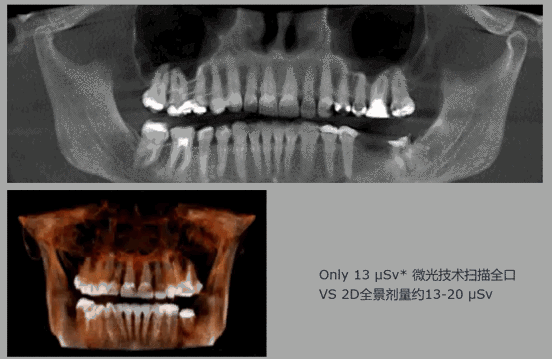

全新X-TREND,震撼将至